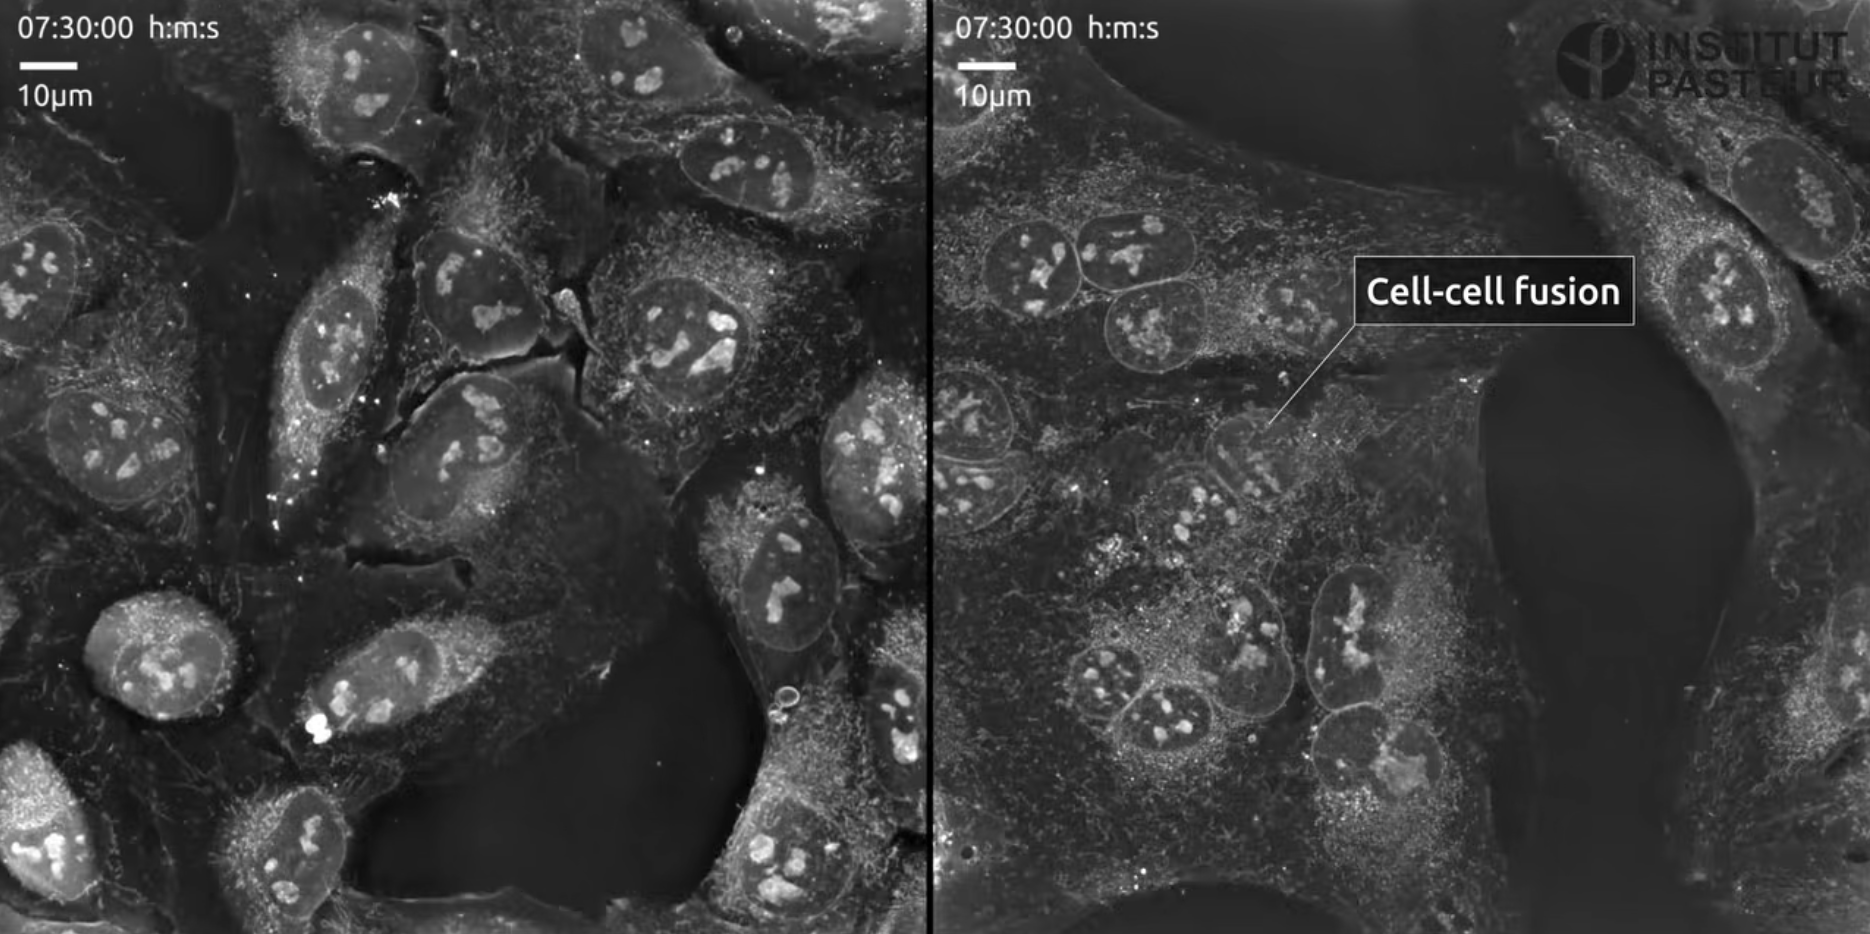

Na obrázku vyššie ^^^ vidíme fúziu buniek vďaka tomu, že Covid použije spike proteín, ktorý aktivuje proteáza zvaná TMPRSS2. No a tú oslabuje fenolová molekula, ktorá je schopná viazať sa do miesta proteázy pri aktivácií Covidu. Aktivácia mnohých vírusov prebieha v kyslom prostredí. Teda som si spomenul na huby, ktoré rastú v kyslých prostrediach a ich antagonistov lišajníky, ktoré sú schopné pri extrakcii fenolovej zložky "zlomiť" TPMRSS2 proteázu. Samozrejme ma zaujala aj koncentrácia lišajníkov jedovatým chloroformom, ale našiel sa aj potravinársky prijateľný etanol, či olivový olej. Logicky, čo musí Covid spraviť, ak je oslabený lišajníkmi? Použiť endocytózu a čakať, ktorá bunka ho zhltne, nefunguje mu však prisatie na bunku, čím je oslabený ako vírus.